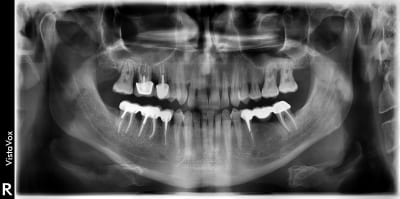

J'avais une pano instrumentarium OP200D avec l'option VT qui permet de faire des coupes transversales (mais que je n'ai jamais utilisé), et là depuis octobre, j'ai la VistaVox de Durr.

Pour ce qui est de la qualité de la 3D, je n'ai aucune référence pour pouvoir comparé, car je n'en avais pas avant... Par contre pour la pano, je peux dire que les clichés de la VistaVox sont quasi comparables qualitativement à ceux de l'intrumentarium...

Ci-joint deux clichés prise sur le même patient à 3/4 ans intervalle.